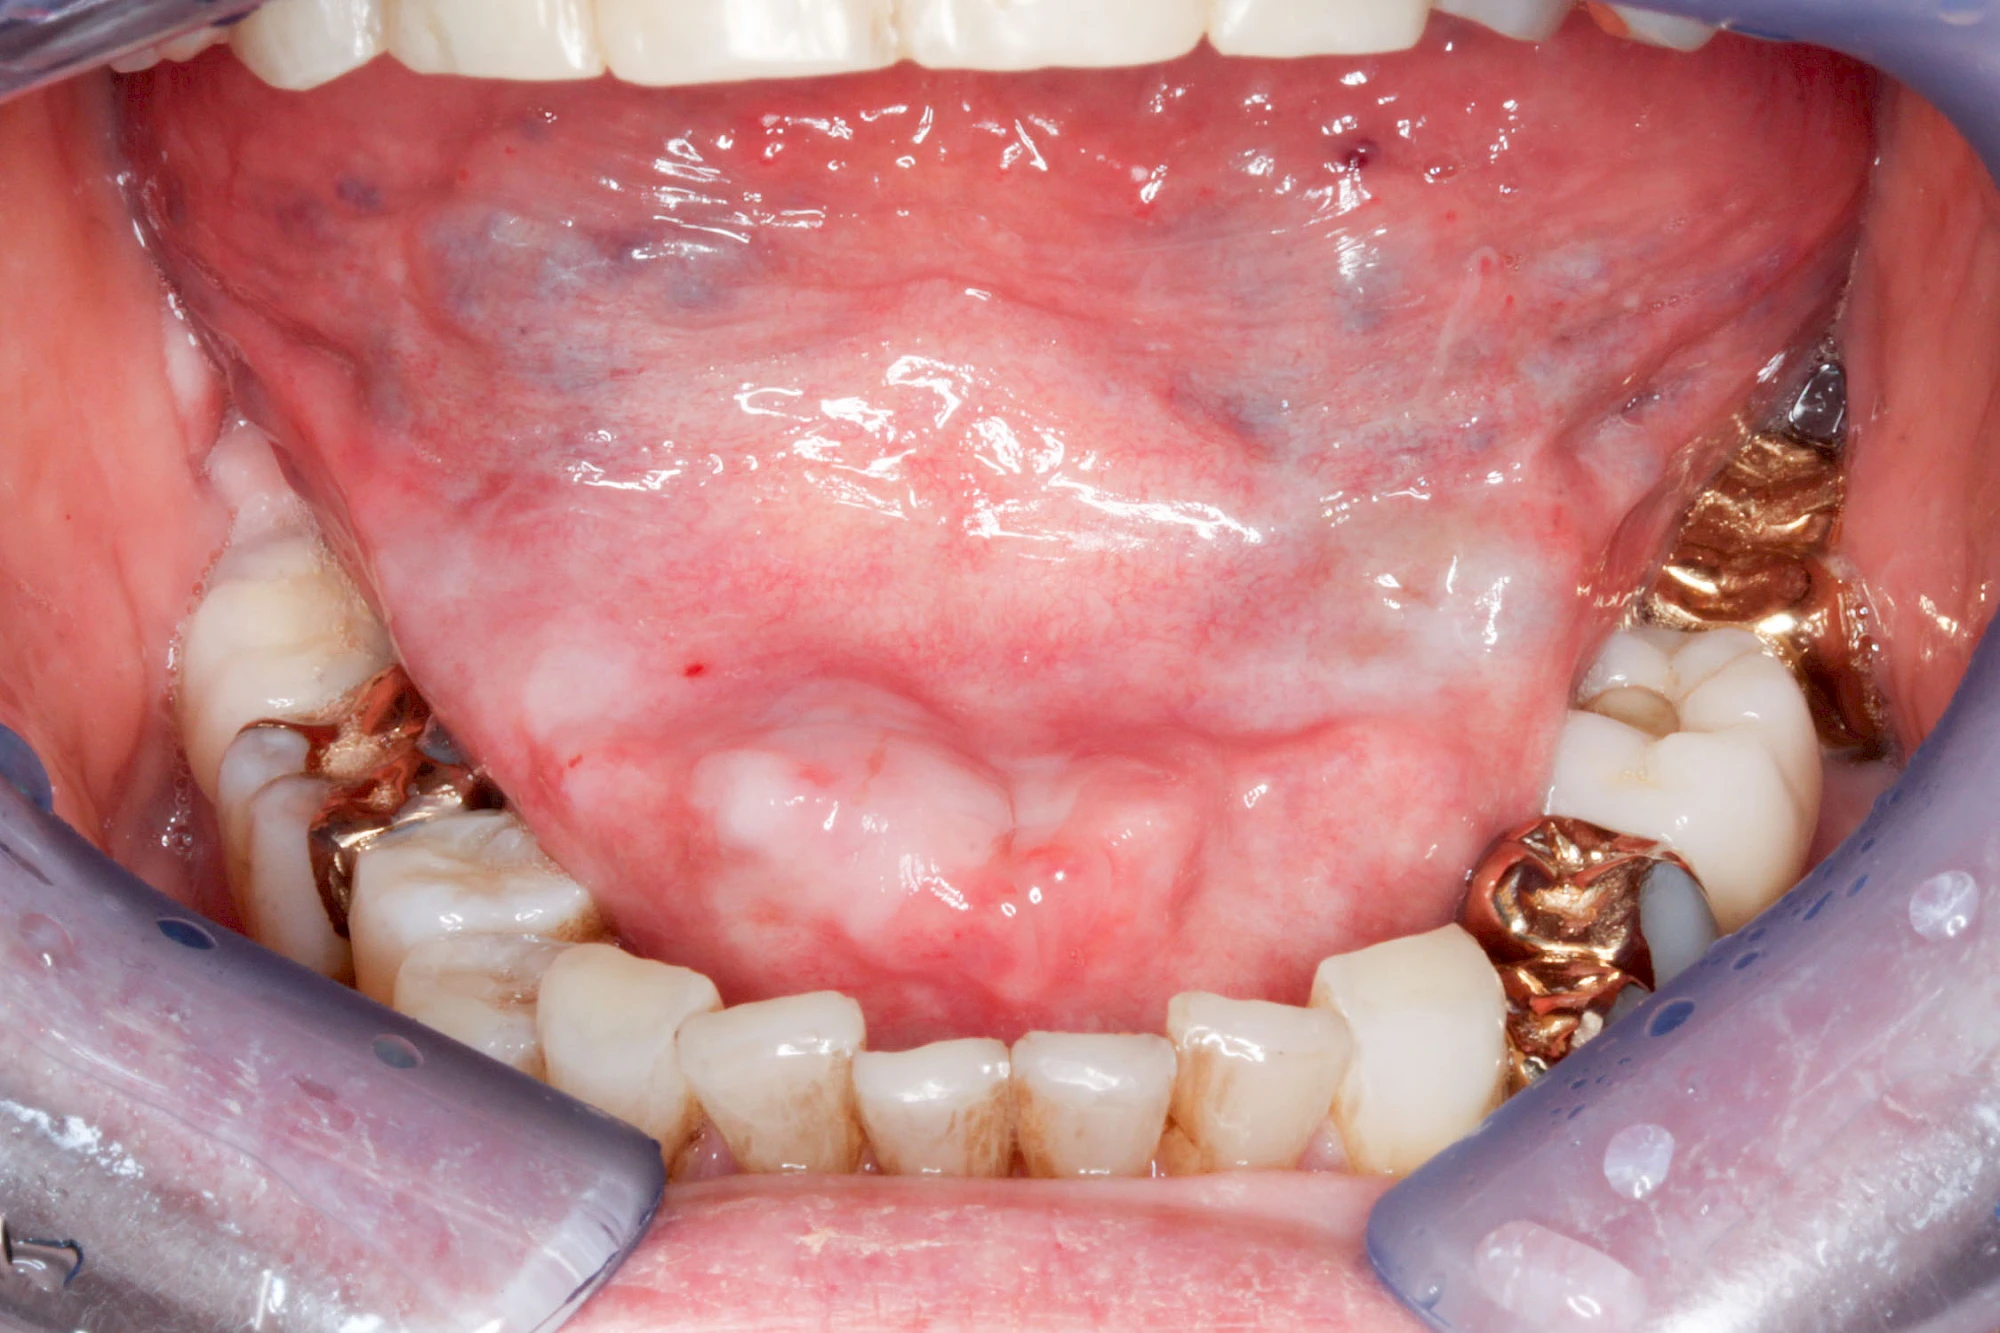

Milchiges bzw. gelbliches Sekret im Bereich der Speichelausführungsgänge entweder an den Wangeninnenseiten auf Höhe der ersten großen Backenzähne im Oberkiefer oder unter der Zunge können auf Entzündungen der großen Spreicheldrüsen hinweisen. Ebenso Schwellungen bzw. Auftreibungen, Rötungen oder spürbare Wärme einseitig unterhalb eines Ohrs und im Bereich des Kieferwinkels.

Speicheldrüsenzyste

Eine Speicheldrüsenzyste (Speicheldrüsenretentionszsyte) kann als Schwellung oder Auftreibung meist im Bereich der größeren Ausführungsgängen auffallen, wenn z. B. ein Speichelstein den Speichelfluss behindert. Vor allem bei den Mahlzeiten, wenn der Speichelfluss angeregt wird, nimmt die Auftreibung oder Schwellung schmerzhaft weiter zu. In der Regel ist die Unterkieferspeicheldrüse (Glandula sublinugalis) betroffen. Man spricht dann auch von einer Frosch- bzw. Fröschleingeschwulst (Ranula). Bringt sanftes Massieren der Schwellung bzw. Auftreibung keine Verbesserung, sollte ein Arzt oder Zahnarzt hinzugezogen werden